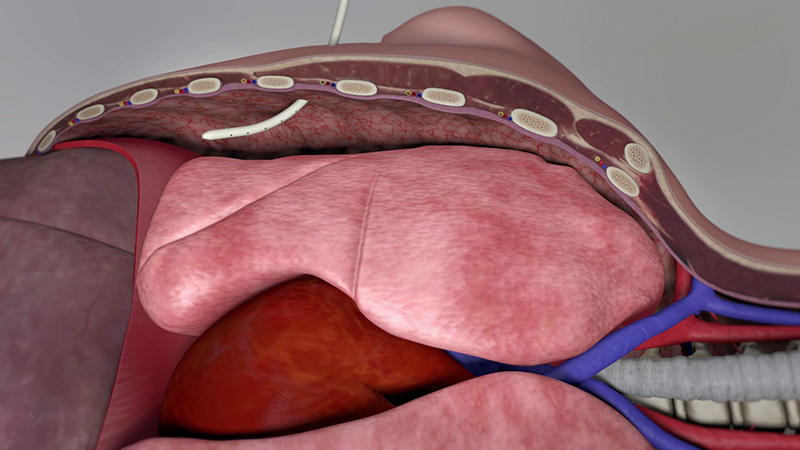

STERITALC ist für alle Indikationen einer Pleurodese geeignet. Es ist unlöslich und induziert eine permanente Pleurodese.

Es gibt veröffentlichte Berichte über zwei große, prospektive Studien zur Bewertung der Sicherheit von intrapleural verabreichtem STERITALC. Eine Studie untersuchte 558 Patienten, die mit STERITALC 4 g durch Poudrage bei MPE behandelt wurden. In der zweiten Studie wurden 418 Patienten mit rezidivierendem primärem Spontanpneumothorax untersucht, die mit STERITALC 2 g durch Poudrage behandelt wurden. Es wurden keine Fälle von ARDS oder talkumbedingten Lungenschäden gemeldet.